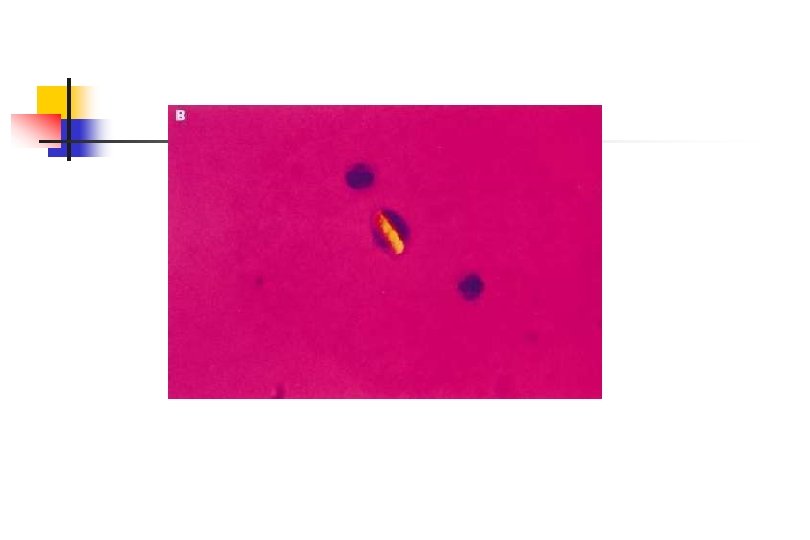

Polarize Işık Mikroskobunda MSU Kristalleri Polarize Işık Mikroskobunda MSU Kristalleri